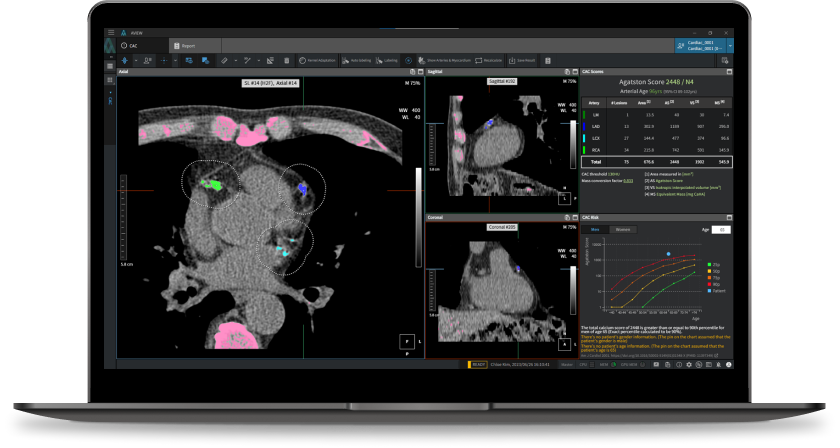

- CT 스캔: 관상동맥 석회화의 상태를 명확하게 볼 수 있는 비침습적인 검사 방법으로, 좌우 심장관의 석회화 수준을 확인할 수 있습니다. 많은 경우, 이 검사는 영화 한 편 보는 시간 안에 가능하여 매우 효율적입니다.